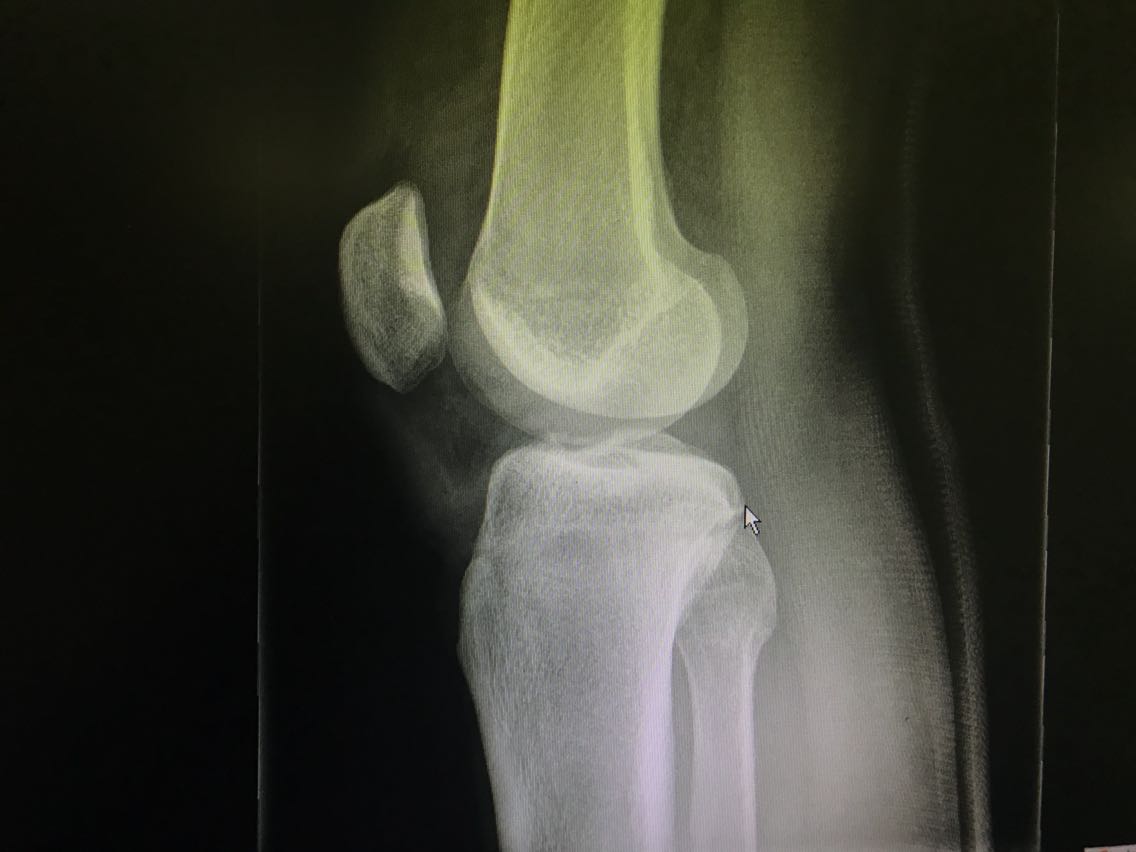

患者男性,26岁。 主诉:打篮球时受伤致右膝关节疼痛、功能障碍3天。 现病史:3天前患者打篮球时跳跃落地后以右足着地致右膝关节受伤,具体不详。伤后即感右膝关节剧痛,伴活动障碍,无意识障碍等不适。就诊于当地医院,给予对症处理后回家休息。3日来患者右膝关节疼痛无缓解,以屈曲时为甚。再次就诊于当地医院,行DR检查示:右胫骨平台骨折。患者为求进一步治疗,就诊于我院,急诊入我科。 既往史无特殊。

查体:右膝关节肿胀,下前方压痛,右膝关节呈强迫伸直位,被动屈曲时疼痛加重。 辅助检查: DR检查示:右胫骨平台骨折。

诊断:右胫骨平台骨折。 治疗:右胫骨平台骨折切开复位钢板螺钉内固定+右膝关节半月板修复+人工骨植骨。

患者打篮球时跳跃落地后受伤,伤后即感膝关节疼痛伴活动受限,经保守治疗疼痛无缓解,此时就应该考虑到胫骨平台骨折的可能。胫骨平台骨折多伴有半月板损伤,需同期修复。